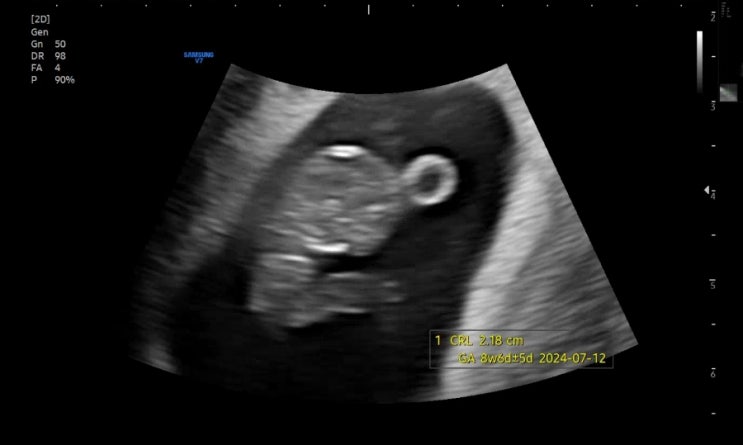

임밍아웃 뜻 시기 부모님 언제 임신안정기 아기심장소리 임신6주 7주

임밍아웃 뜻 시기 부모님 언제 임신안정기 아기심장소리 임신6주 7주 임신 테스트기에 떡 하니 두 줄! ...

임신4주차 - 임신8주차 기록 임테기진하기 / 임밍아웃

임신기록이라니 되게 설레네요 임신초기 다들 공감하실거에요 여기저기 티내고싶지만 혹시나 하는 마음에 ...